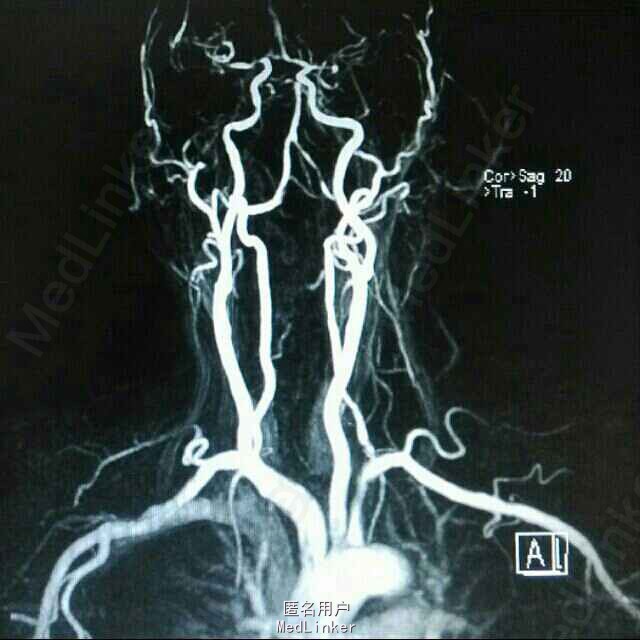

查体:BP 136/84mmHg,抬腿右下肢较左侧差,余无明显异常。 辅检:6-8 D-D 1.87,FIB 7.15,ALT 38,AST 46,GGT 37,LDL-C 4.38,铁蛋白 320,CRP 96.7,ESR 70,尿酮体1+ 6-15 PLT 469,ALT 53,GGT 50,ESR 38,D-D 0.59 血糖监测:早餐后高 彩超多普勒:升主动脉较宽,左室舒张功能减低;双侧颈动脉粥样硬化斑形成。 经颅多普勒:双侧颈内动脉、颈外动脉、左侧颈总动脉血流速度减慢;左侧锁骨下动脉、右侧大脑中动脉、大脑前动脉、左侧颈内动脉虹吸部管腔呈收缩状态;左侧颈内动脉虹吸部管腔重度狭窄;各检查动脉管腔应硬化。 头部MR、脑动脉造影MRA:脑干右侧11*12mm梗塞灶;腔隙性脑梗塞;脑萎缩;双侧额部顶部硬膜下积液;左侧椎动脉起始段及椎动脉-基底动脉汇合段管腔中度狭窄,双侧颈总、颈内外动脉、双侧大脑前中后动脉多发中-重度狭窄,动脉粥样硬化表现。

诊断:脑梗塞;高血压病3级 极高危;糖尿病 2型;动脉粥样硬化;高脂血症;慢性胃炎 治疗:依达拉奉、马来酸桂哌齐特、丹森川穹嗪注射,小牛血清去蛋白注射液;硝苯地平缓释片;阿司匹林肠溶片;阿托伐他丁钙片;阿卡波糖片。